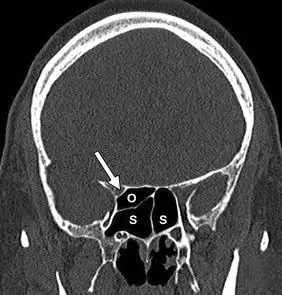

冠状未增强ct扫描显示蝶窦(s)中的右侧蝶窦(onodi)小室(o.